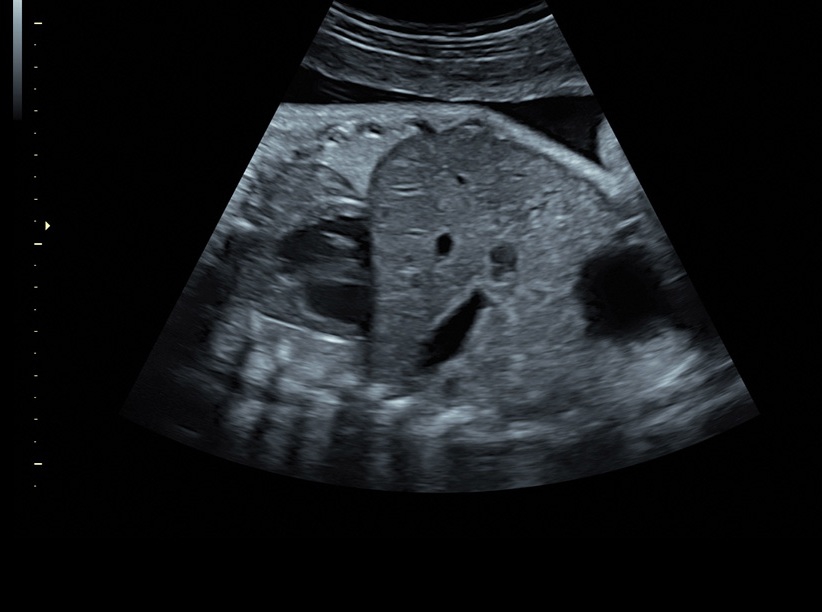

Ультразвуковая платформа Voluson S8 представляет собой оборудование экспертного класса с передовыми возможностями и высоким уровнем автоматизации процессов. Она позволяет проводить сканирование в режимах 2D, 3D и 4D с высоким качеством изображений.

Аппарат Voluson S8 базируется на надежной платформе VCA, которая имеет множество положительных отзывов. Она обладает высококонтрастной технологией объемной реконструкции, обеспечивая качественное воспроизведение изображений. Информация выводится на широкоформатный цветной монитор размером 23 дюйма для убедительной демонстрации плода будущим родителям и облегчения работы врача.

• Высокое качество изображений: Voluson S8 обеспечивает высококачественные изображения, позволяющие детально оценить состояние плода и обнаружить возможные патологии.

• Технология автоматической фетометрии в 2D режиме (SonoBiometry): Эта технология позволяет автоматически измерять бипариетальный размер, окружность головы, окружность живота, длину бедра и плеча плода, обеспечивая точные и надежные измерения.